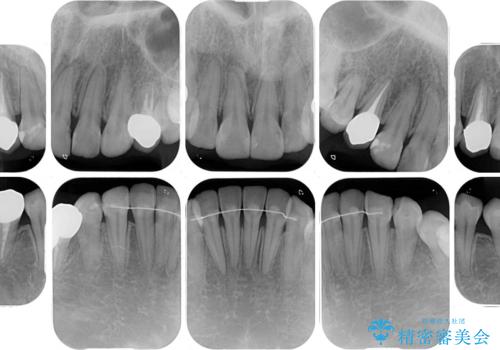

総合歯科治療 矯正治療と失活歯のセラミック補綴治療

- 失活により変色した歯と不揃いな口元を気にして来院された患者様です。

口元をインビザラインにより歯列を整え、その後に失活している奥歯をオールセラミッククラウンにて補綴治療することとしました。